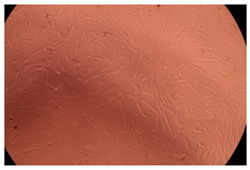

2.6. In Vivo Evaluation of the IOP

3.2.4. In Vivo Tests

| Sample | IOP (mmHg) | |||||

|---|---|---|---|---|---|---|

| After 15 Days of DEX Administration | After 15 Days of Treatment | |||||

| Morning | Noon | Evening | Morning | Noon | Evening | |

| LC | 5 | 6 | 7 | 5 | 6 | 7 |

| LE1 | 9 | 10 | 11 | 9 | 10 | 11 |

| LE2 | 9 | 10 | 11 | 9 | 10 | 11 |

| LE3 | 9 | 10 | 11 | 7 | 8 | 9 |

| LE4 | 9 | 10 | 11 | 4 | 5 | 5 |

| LE5 | 9 | 11 | 12 | 10 | 11 | 13 |